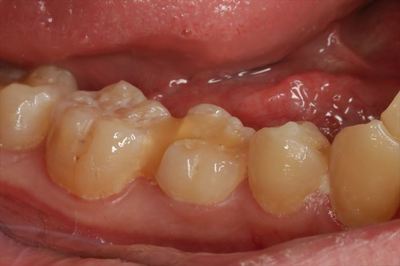

実際の右下臼歯です。

デュラシールのような半軟性樹脂仮封材の内部に白いセメント裏装が透けています。

予定では次回、金属の詰め物のセットであったそうですが、ここから弊オフィスで治療を引き継ぎます。

大きな病院の歯科において「強度的に金属でないとダメだ」とお聞きになって弊オフィスにご来院です。